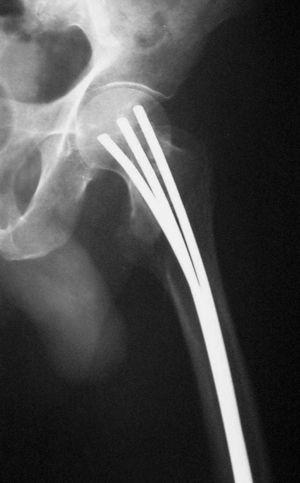

Estos dos sistemas abogan por síntesis rígidas, desechando la idea propuesta por Ender 5 , donde la elasticidad de la síntesis endomedular, asociada a la orientación en las tres direcciones del espacio dentro de la cabeza femoral, conseguía la estabilización y consolidación de estas fracturas (fig. 1).

Figura 1. Correcta posición en la cabeza femoral de los clavos de Ender en una fractura pertrocantérea.